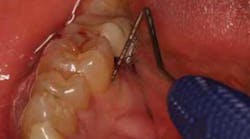

To achieve predictable periodontal therapy results, a guided bone/tissue regeneration procedure (GTR/GBR) is indicated that includes the use of bone-grafting products (e.g., enamel matrix derivative) to regenerate the lost tissue and, most importantly, the bone. (5-8)